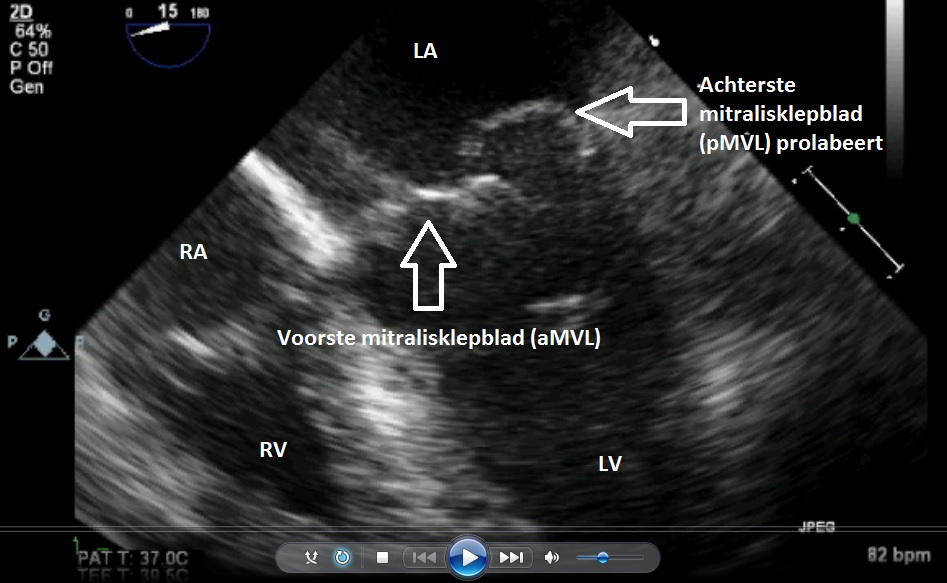

Video 1 slokdarmechocardiografie van de mitralisklep vóór de operatie

Video 2 slokdarmechocardiografie van de mitralisklep vóór de operatie